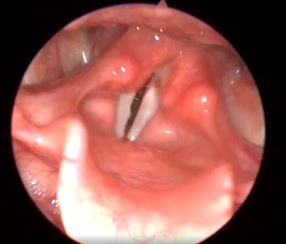

Клинический пример №3. Коагуляция расширенного сосуда правой голосовой складки с использованием лазера с длинной волны 445 нм.

Восстановление нормальной слизистой оболочки без признаков воспаления в быстрый период

Рис 3А. Расширенный сосуд средней трети правой голосовой складки. До операции.

Рис 3Б. Расширенный сосуд средней трети правой голосовой складки. 10 дней после операции.